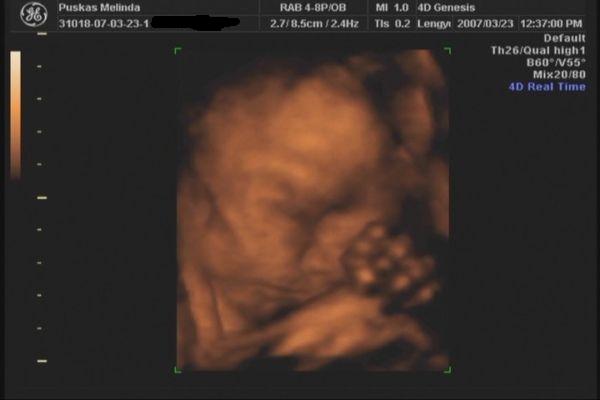

Tegnap voltunk 4D-n. gyönyörű egészséges 31 dekás kislány. :D A Lara Boglárka nevet kapja tőlünk. :) egy kép róla meg egy a pocakról. :)

Kép Kép